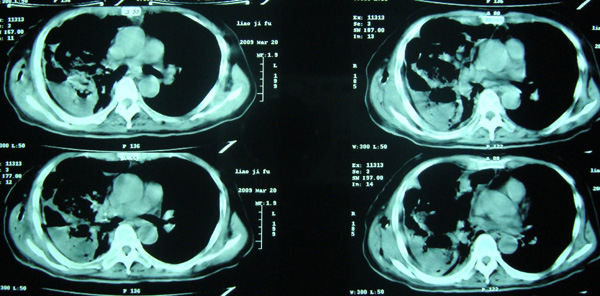

经治疗至17日胸闷痛摄片如9号图,20日复查如7,8号片.

结论:右侧大量胸腔积液,可疑膈下脓肿.

20日院外ct检查,片示于后.

1)考虑右肺感染性病变(化脓性肺炎或肺脓肿可能)。2)右侧液(脓)气胸,部分包裹。

考虑1、右膈下脓肿并肺脓肿,2、右侧液气胸

右肝上间隙积液,支持考虑膈下脓肿,

右侧脓胸、右膈下脓肿。不除外右肺化脓性肺炎。

膈下可见气液平面,结合临床应该考虑膈下脓肿并同侧胸腔积液(脓)

右侧膈肌抬高明显,胸腔内无明显积液,表现为胸膜反应,肝脏周围大量积液,并见多个液气平面。右下肺不均匀密度增高影。结合临床考虑右侧膈下脓肿并腹腔内积液、右下肺并发感染及胸膜反应,节段性肺不张不除外。

右肺下叶见大片状病灶,密度不均,其内见透光区。沿右侧胸壁见多发含气腔,其间可见间隔,其内部分可见液平。膈肌下未见异常(纵隔窗窗位太低)。应该是典型的化脓性肺炎合并脓胸。

右隔下积脓并右侧肺脓肿;右侧液气胸